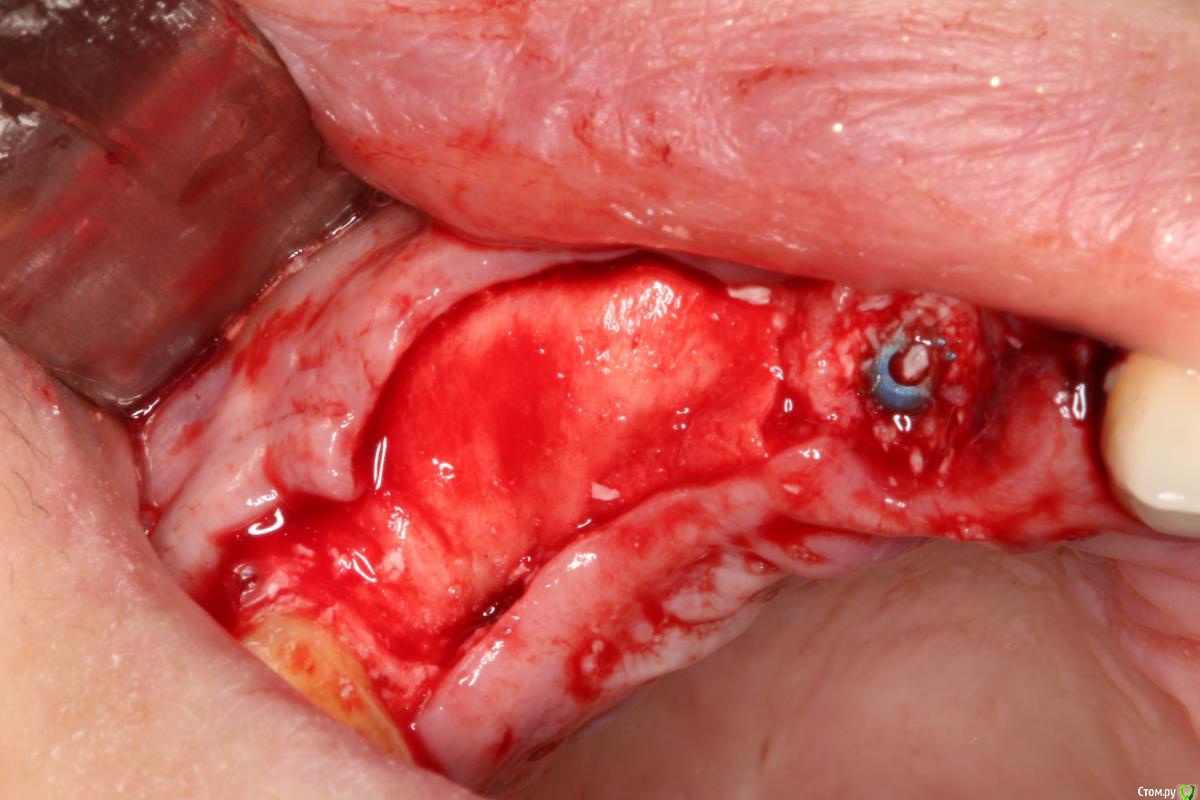

Robinbobin Опубликовано 9 сентября, 2015 Поделиться Опубликовано 9 сентября, 2015 Зуб 1.1 удалил,кюретаж и одномоментно установлен имплантат, заполнил MP3 и закрутил заглушкуУстановил имплантаты в области 1.3,1.4 подсыпал так же MP3 под мембрану и запинилЕсли покажите пальцем на ошибки буду благодарен))) 4 Ссылка на комментарий